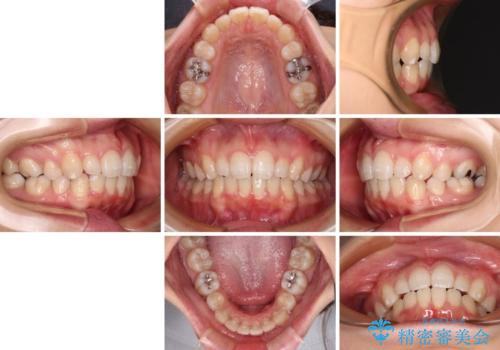

抜歯矯正の後戻り インビザライン・ライトによる矯正治療

治療途中、妊娠・出産があり、1年近く治療が停滞しましたが、無事に終了することができました。

治療のゴールも変更できないため、軽微な歯列不正や、後戻り改善などに適しています。